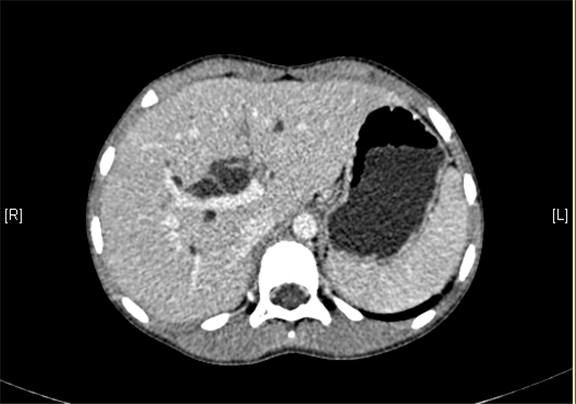

上腹部增强CT:肝内外胆管扩张,考虑胆管囊肿(以左右肝管、肝总管及胆总管扩张明显)可能性大。

术前CT检查:

动脉期